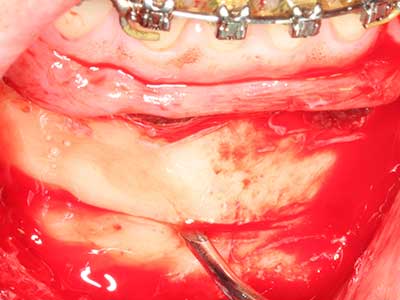

En la extracción de bloques óseos la piezocirugía también presenta ventajas adicionales: Además de la alta precisión en la osteotomía que ya se ha descrito antes, se ha comprobado que el uso de los delgados insertos de sierra resulta especialmente cuidadosas con el hueso. Frente a esto, sobre todo cuando se usan las fresas de Lindemann, cabe esperar pérdidas en la extracción significativamente más altas debido al mayor grosor de la parte frontal del cabezal (Lakshmiganthan, Gokulanathan et al. 2012). La separación basal que se necesita en particular en los injertos de bloque extraídos de forma retromolar se ve facilitada mediante sierras perpendiculares especialmente previstas a tal fin, lo que permite considerar que la cirugía piezoeléctrica es un procedimiento preciso y seguro para la obtención de bloques de hueso en el área retromolar (Happe 2007) (fig. 1-12).

Fig. 3: La separación basal del bloque se ve facilitada con piezas dotadas de una angulación especial.

Fig. 4: Con la rasqueta ósea se obtienen virutas adicionales de hueso autógeno.

Fig. 5: Comprobación de las dimensiones del bloque en la zona de recepción.